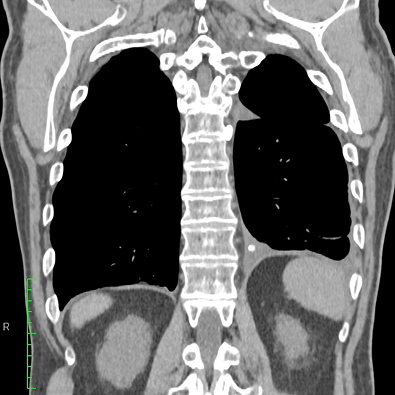

In a study patient, fluid occupying nearly half of the hemithorax at baseline was significantly reduced by 30 days and remained low at 60 days, demonstrating consistent drainage and lung re-expansion over time.

CT Baseline

30 Days

60 Days